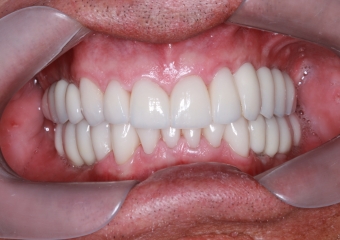

Facetas e dentes em porcelana sobre implantes